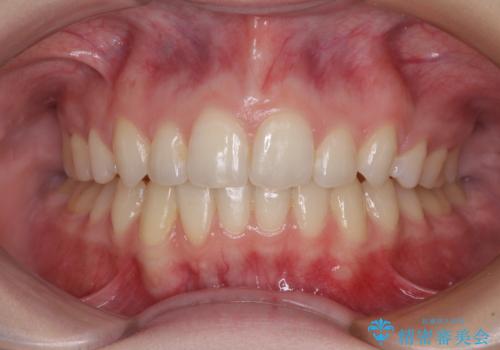

ワイヤー装置にて矯正治療を行っていましたが、急な転勤で毎月の通院が難しくなってしまいました。

抜歯したスペースは概ね閉じていたので、インビザラインに切り替えて通院回数を減らし、治療を継続していくこととしました。

突出していた口元がスッキリと仕上がり、患者様には大変満足していただきました。